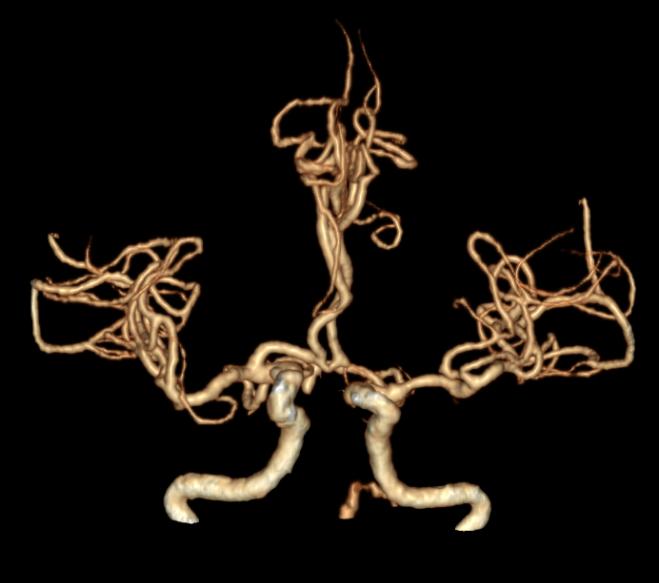

更棘手的是,老人为III型主动脉弓,右侧椎动脉为优势血管,血管迂曲度大,解剖结构非常复杂。医院神经内科团队从常规的股动脉入路尝试取栓,却遭遇了多次失败。

手术台上,凭借多年的介入经验和精湛的技术,神经内科余传庆主任团队反复调整导管角度,最终成功超选进入右侧椎动脉,随后BASIS技术为患者进行球囊扩张,顺利取出了血栓,再植入药物洗脱支架,保障血管通畅。“当DSA屏幕上清晰显示血管完全开通时,我们所有人都长舒一口气——患者的生命保住了。”